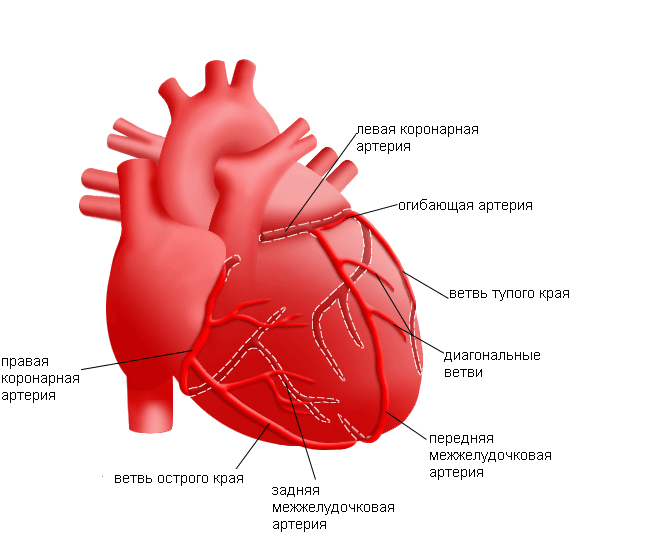

Особенности и диагностика левостороннего кровотока